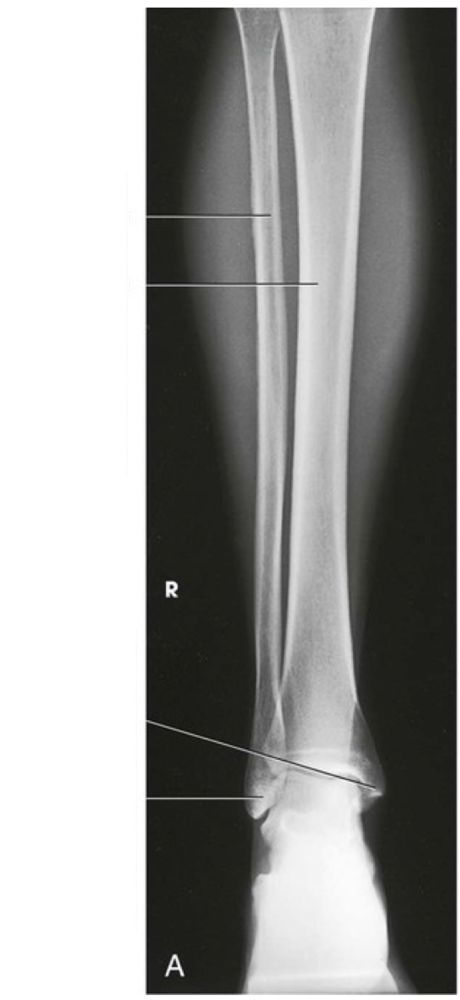

Question

Label the image

Image:

eb699ddf-4ad6-4afb-84ec-2da24a3fba05 (image/png)

Answer

fibula

tibia

medial malleolus

lateral malleolus